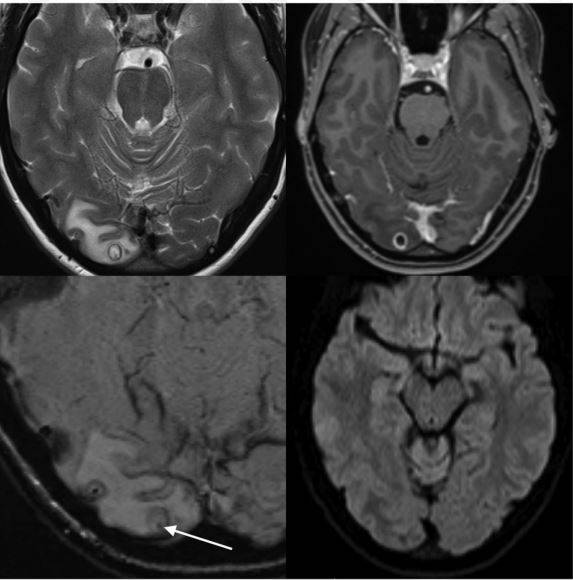

澳洲一名25岁女子经历一个多礼拜的头痛后,去医院接受磁振造影(MRI)检查,原本医生以为是肿瘤造成她头痛的原因,但在手术时惊觉那不是肿瘤,而是「充满绦虫幼虫的肿囊」,成为澳洲感染绦虫的首位病例。

而在过去7年中,这名女子每个月发生头痛的症状大约2到3次,然而最近头痛的频率却持续了一个多礼拜,有时还会伴随视线模糊的状况,因此才会就医检查,在医生取出肿囊后,已无需进一步治疗。